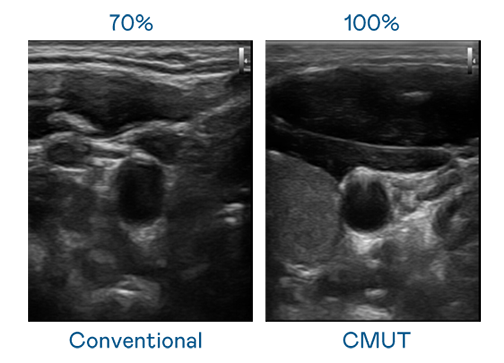

CMUT 技术是一种用电容式微机电元件来产生超音波讯号的技术。与传统 PZT 压电式技术相比,CMUT 频宽增加 30%,更宽频的超音波讯号让影像解析度大幅提升,是实现高影像品质医疗超音波扫描、促进精准医疗发展的关键技术。

大频宽带来超清晰影像

超音波影像的解析度高低,首先取决于探头能发出的讯号频宽。350vip8888新葡的京 CMUT 可提供高清晰的超音波讯号,提供高频宽、高灵敏度、影像纹理细节更高的超音波影像,协助医护人员缩短影像判读时间及利用精准的医疗影像进行诊断。